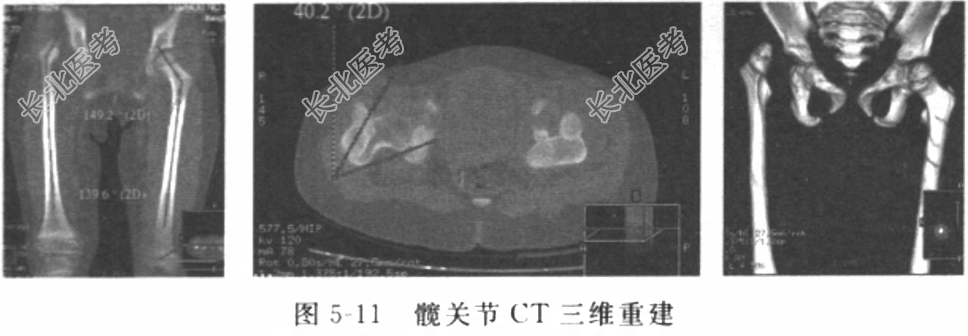

诊疗计划:①按骨科护理常规,二级护理;②指导患者家属术前髖“人”字石膏托外固定后的护理及术后患儿在术区大小便等个人卫生的护理;③进一步完善各项检查,待条件允许时,择期行手术治疗。患者入院以来,生命体征稳定,无咳嗽、咳痰等异常;手术区皮肤无破溃,皮肤完好。诊断明确,入院后检查血常规、生化全套、尿常规、粪常规、凝血四项、心电图、胸部X线片等均提示重要脏器功能未见明显异常;髋关节CT三维重建(图5-11)示右颈干角为149.2°,右前倾角为40.2°患者年龄已2岁7个月,髖白骨骼的塑形能力较低,非手术疗法的效果欠佳。综合以上情况,故该患者有手术指征。